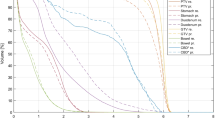

Magnetic field influence

The RT plans of all patients in this study met the acceptance criteria. In Figs. 4, 5, 6 and 7, the distribution of doses to different organs among the plans are represented by column charts. The horizontal axis of the chart shows the DVH indicators and evaluation parameters. In the cases where DVHs is CI and HI, the vertical axis displays absolute values. In the cases where DVHs is Dx, the vertical axis displays the percentage of the prescription dose, and in the case of Vx, it displays the volume percentage that accepts the xGy value. Additionally, majority of the characteristics between groups showed variations. Asterisks were used to indicate the DVH parameters that differed significantly (P < 0.05). The Wilcoxon symbolic rank sum test is employed, and the parameters all fit the non-normal distribution.

The dose-volume difference between the treatment plans designed for 1.5 T and 0 T for the first quadrant is shown in Fig. 4. In the indicators involving PTV coverage and HI, there were statistically significant differences. For PTV, in the absence of a magnetic field, the indexes of most recalculated optimized plans were significantly improved, including an increase in PTV Dmin (97.75 ± 17.55 vs. 100.96 ± 22.78)%, a decrease in Dmax (121.48 ± 29.68 vs. 119.06 ± 28.52)%, and a decrease in HI (1.14 ± 0.14 vs. 1.05 ± 0.01). Some indexes also deteriorated significantly, including the increase in D98 (101.35 ± 7.42 vs. 109.35 ± 26.52)%. In the absence of a magnetic field, most of the indicators for OARs increased, but there were no significant differences.

The difference in dose-volume measurements between the treatment plans designed for 1.5 T and 0 T for the second quadrant is shown in Fig. 5. In the indicators involving PTV coverage and HI, there were statistically significant differences. For PTV, in the absence of a magnetic field, the indexes of all recalculated optimized plans were significantly improved, including an increase in PTV Dmin (84.33 ± 19.74 vs. 89.96 ± 21.23)%, a decrease in Dmax (105 ± 25.08 vs. 104.05 ± 24.86)%, and a decrease in HI (1.04 ± 0.25 vs. 0.99 ± 0.24). In the absence of a magnetic field, most of the indicators for OARs were reduced, but there were no significant differences.

The dose-volume difference between the treatment plans designed for 1.5 T and 0 T for the third quadrant is shown in Fig. 6. In the indicators involving PTV coverage and HI, there were statistically significant differences. For PTV, in the absence of a magnetic field, the indexes of most of the recalculated optimized plans were significantly improved, including decreases in PTV Dmax (110.21 ± 2.22 vs. 102.31 ± 26)%, L-P V30 (10.66 ± 9.19 vs. 102.31 ± 3.22)% and HI (1.09 ± 0.02 vs. 0.98 ± 0.25). Some indexes also deteriorated significantly, including the decrease in PTV Dmin (92.12 ± 4.92 vs. 89.1 ± 22.35)%. In the absence of a magnetic field, most of the indicators for OARs were reduced, but there were no significant differences.

The dose-volume difference between the treatment plans designed for 1.5 T and 0 T for the fourth quadrant is shown in Fig. 7. In the indicators involving PTV coverage and HI, there were statistically significant differences. For PTV, in the absence of a magnetic field, the indexes of most recalculated optimized plans were significantly improved, including an increase in PTV Dmin (89.78 ± 6.72 vs. 93.04 ± 4.86)% and a decrease in HI (1.09 ± 0.01 vs. 1.05 ± 0.01). Some indexes also deteriorated significantly, including the increase in D98 (99.82 ± 0.82 vs. 100.54 ± 0.84)%. In the absence of a magnetic field, most of the indicators for OARs were reduced, but there were no significant differences.